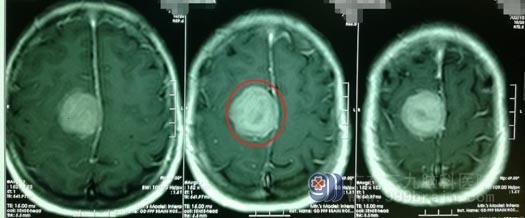

▲安大姐影像检查

从影像检查结果来看,患者大脑右侧额顶镰旁的占位性病变应该是脑膜瘤。肿瘤直径约3.5cm,已经压迫到周围神经,这才导致她出现头痛、肢体无力等症状。随后,鲁明团队为安大姐实施右侧额顶部镰窦脑膜瘤占位切除术,成功为她切除了一颗大小约3.7cm*3.6cm*3.4cm的肿瘤。